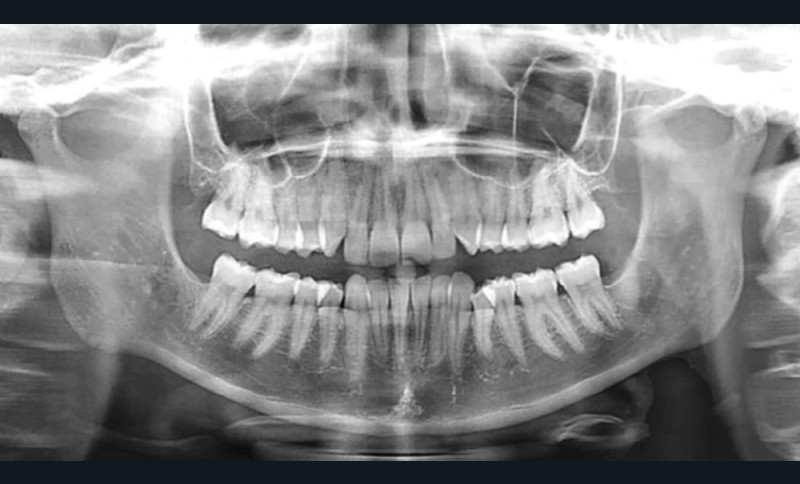

La radiographie panoramique et la téléradiographie de profil objectivent (fig. 3 et 4) :

- un espace rétro-molaire suffisant pour une distalisation ;

- des axes radiculaires molaires favorables à un redressement ;